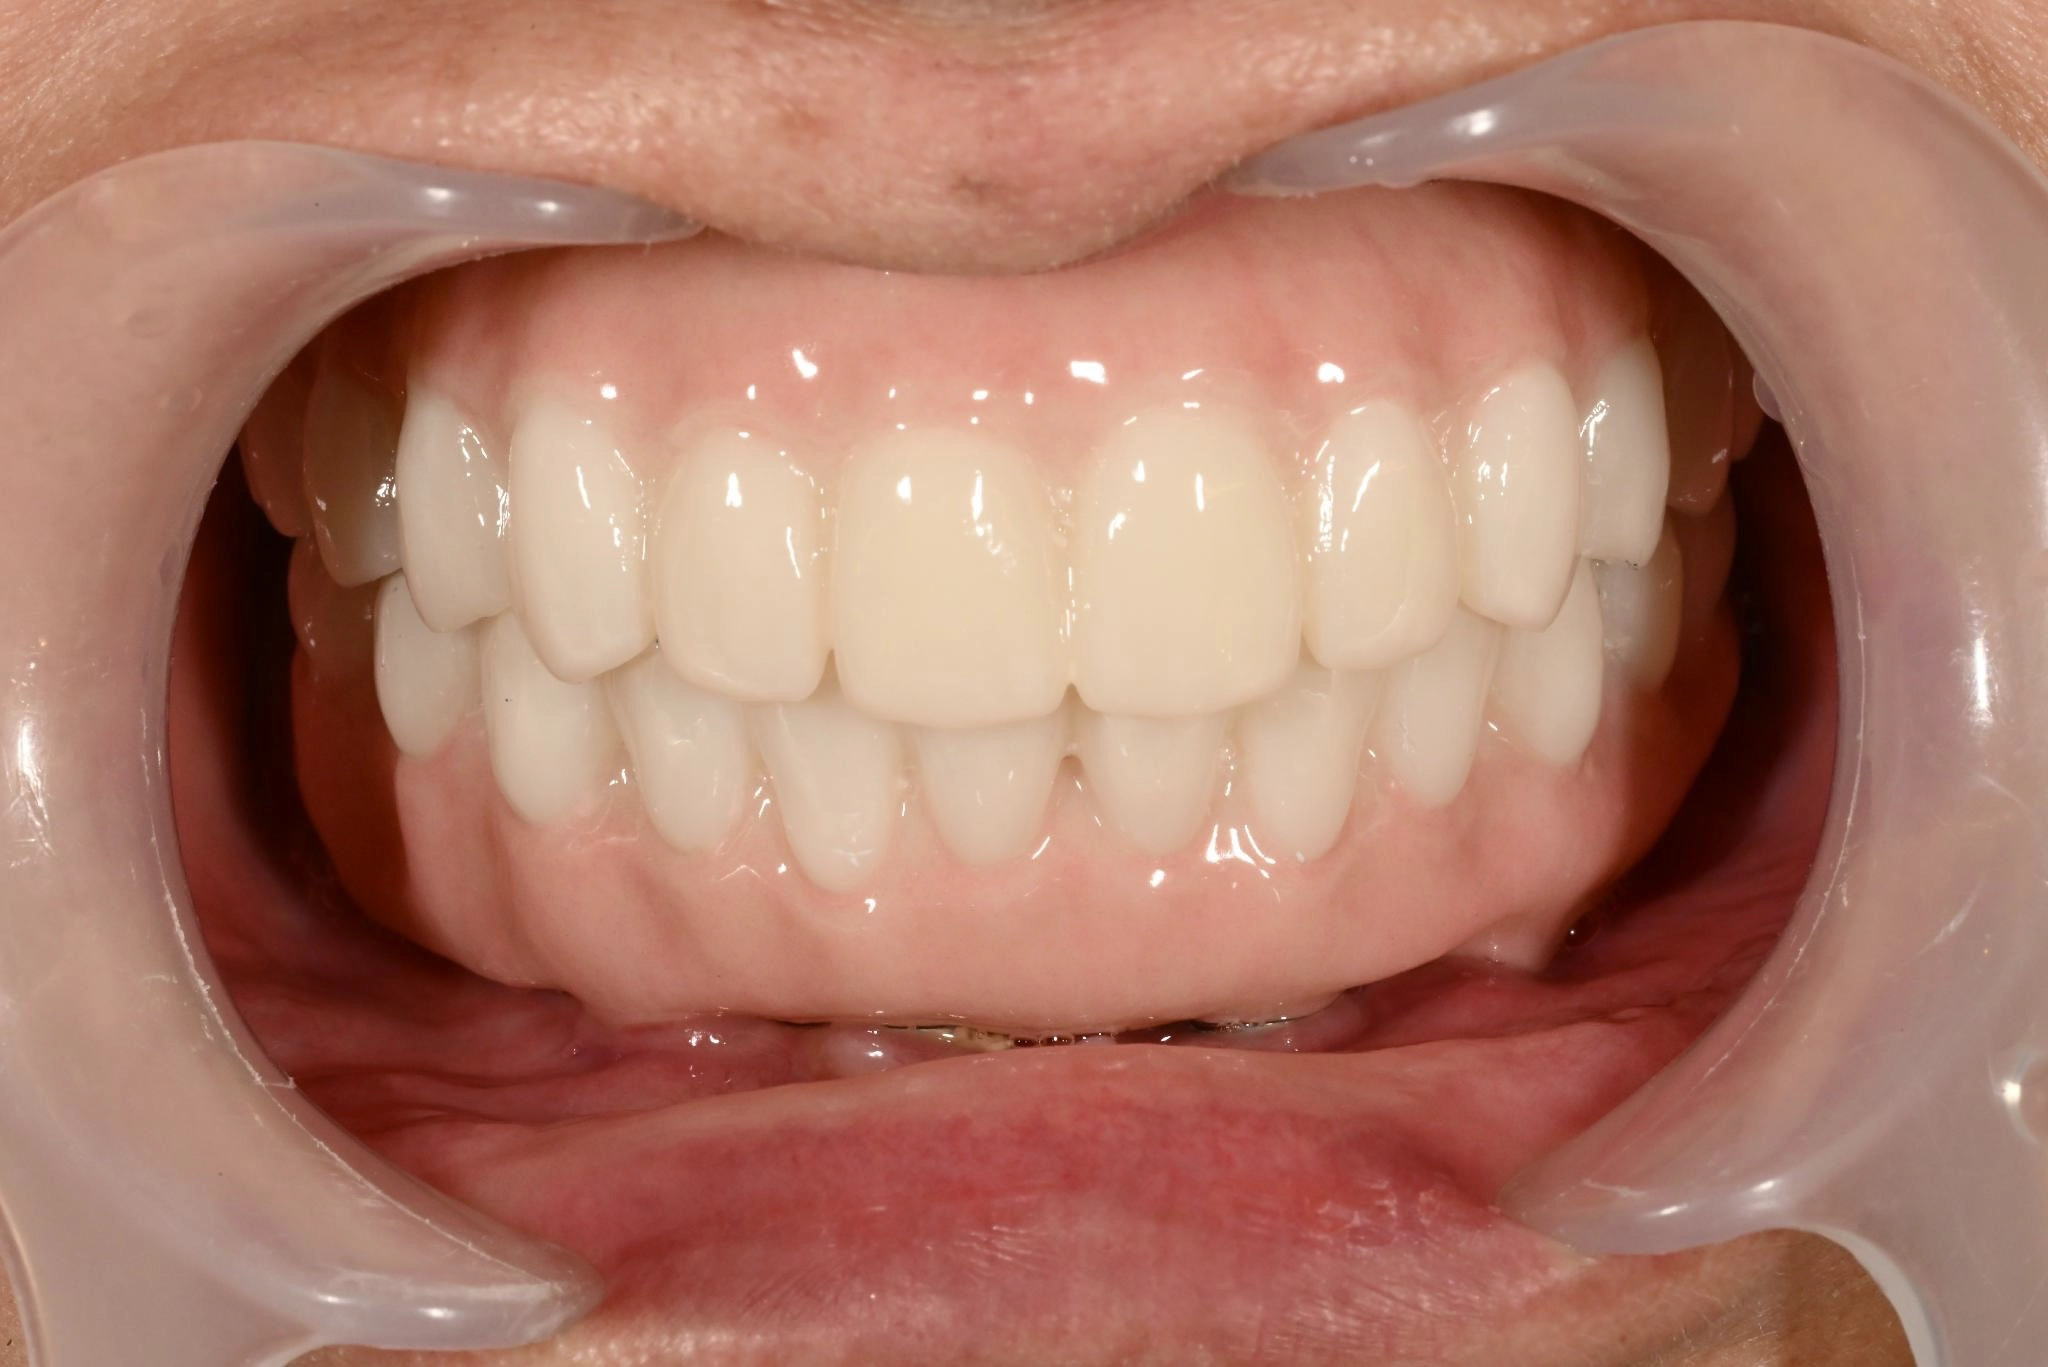

術後

内容 :上下顎オールオン4ザイゴマ4

費用 :5,500,000円

※モニター価格

期間 :半年

リスク:出血・腫れ・痺れ・痛み

術中は特に痛みを感じることはなく、気づいたらいつの間にか終わっていました。術後、これまでの歯の状態と比べて綺麗になっていてとても満足しています。